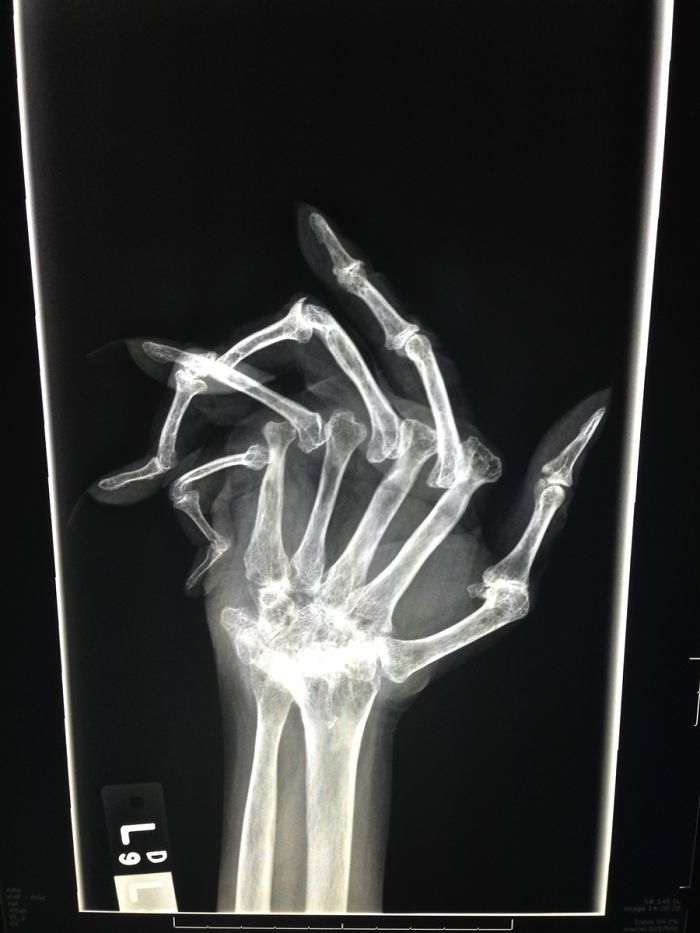

Запущенный ревматоидный артрит — приятного мало